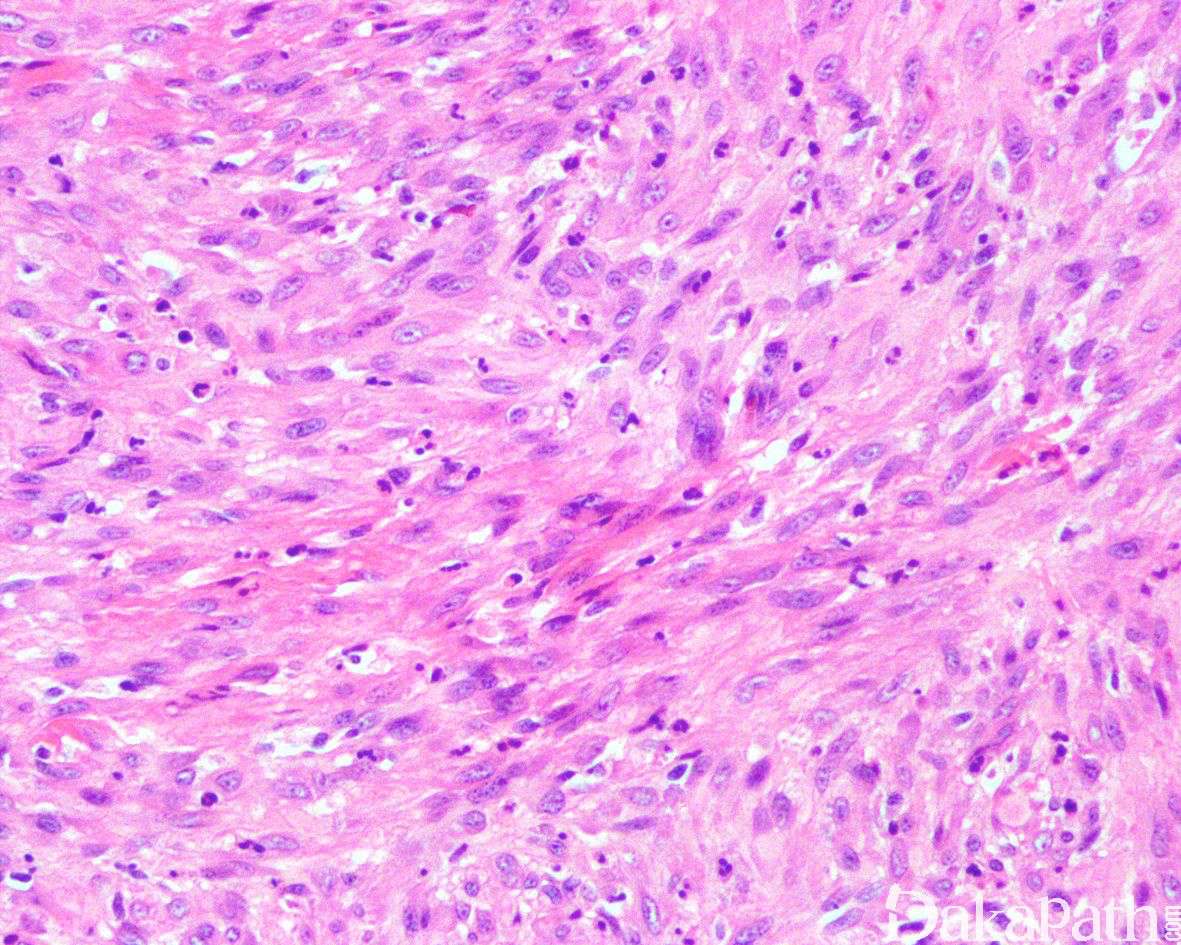

3. 肿瘤细胞呈密集片状或不规则束状或丛状排列浸润至皮下脂肪组织和肌肉组织内;

4. 瘤细胞胖梭形,部分呈上皮样,具丰富的嗜酸性胞质;

5. 上皮样细胞可呈上皮样肉瘤样细胞或横纹肌母细胞样;

6. 无明显血管腔或出血,偶见局部的胞浆空泡提示血管内皮细胞分化;

7. 瘤细胞多形性不明显,核空泡状,具小核仁,核分裂像少见,通常少于 2/10HPF;

9. 背景中可见弥漫散在的中性粒细胞浸润,极少数可见液化性坏死,通常无上皮样肉瘤可见的地图状肿瘤性坏死;